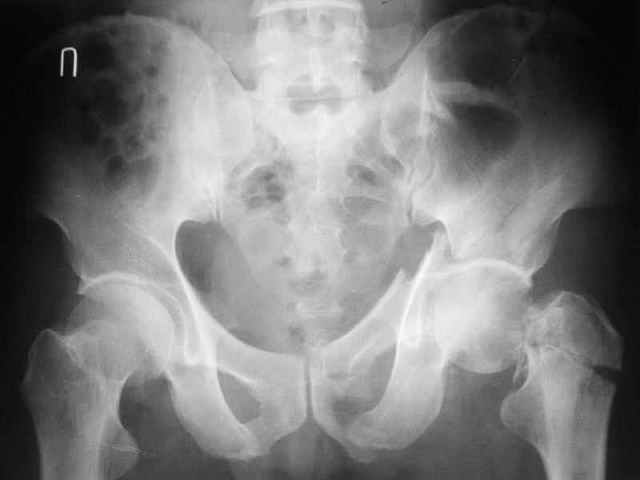

При поступлении в госпиталь 3.06.03

Больной 18 мая 2003 года в автоаварии получил перелом левой вертлужной впадины, вывих бедра. Госпитализирован в один из стационаров области.Вывих вправлен. В последствии бедро вывихивалось еще дважды. На консультацию был представлен снимок от 19.05.03г., больной переведен к нам 3.06.03г. Снимок при поступлении - перелом впадины, задне-верхний вывих бедра. 05.06.2003 г. выполнено открытое вправление вывиха левого бедра и остеосинтез стенки вертлужной впадины двумя винтами. Послеоперационный период без осложнений. Объем движений в левом тазобедренном суставе восстановился полностью. Выписан на амбулаторное лечение в удовлетворительном состоянии с рекомендациями 3 месяца ходить на костылях без нагрузки на оперированную конечность. На контрольных рентгенограммах левого тазобедренного сустава 13.10.2003 г. - признаки консолидации перелома; плотность, форма головки и состояние суставных поверхностей удовлетворительные. Разрешена дозированная осевая нагрузка, на конечность с использованием дополнительной опоры. 19.12.2003 г. больной обратился с жалобами на боли в левом тазобедренном суставе. На рентгенограммах левого тазобедренного сустава 19.12.2003 г., 20.02.04г. - асептичекий некроз головки бедра. 5.04.04г. - эндопротез. Сейчас ходит без трости, не хромает. Особенность эндопротезирования - при удалении винтов прослежена линия перелома заднего края впадины и предложено установить чашку несколько меньшего диаметра, чтобы она была покрыта несломанной частью.